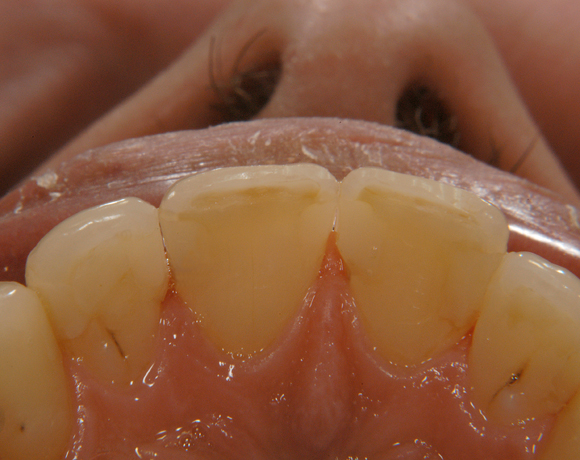

Bildlegende:

Bild 01 – 03: Ausgangssituation mit kariösen Läsionen und insuffizienten Füllungen